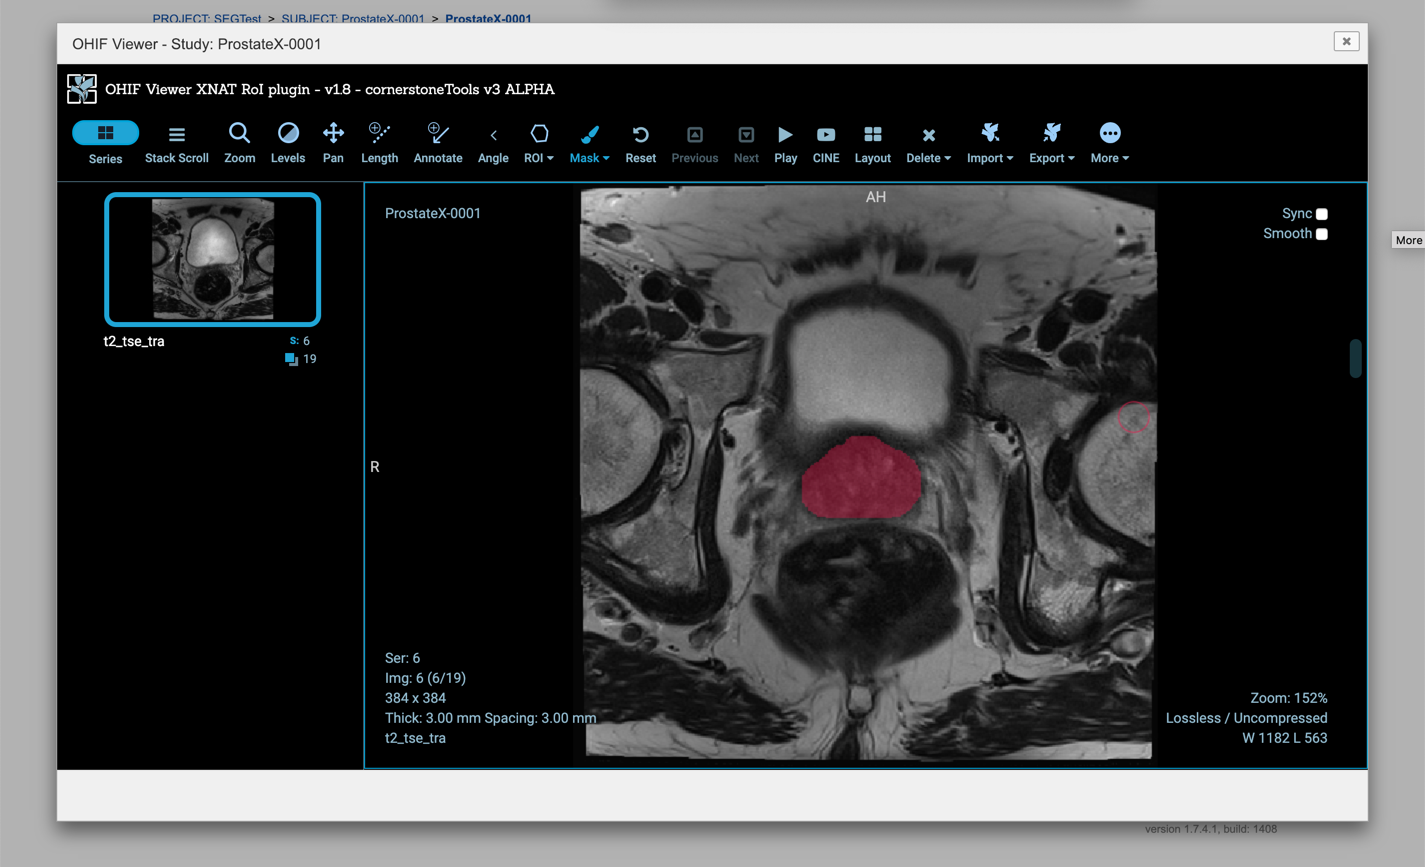

- Installed XNAT with the OHIF plugin (very easy and “just works”!):

Interpolation for contours in XNAT (Soon to be packaged as freely available Cornerstone/OHIF plugins)

RTSTRUCT fetch/view in XNAT